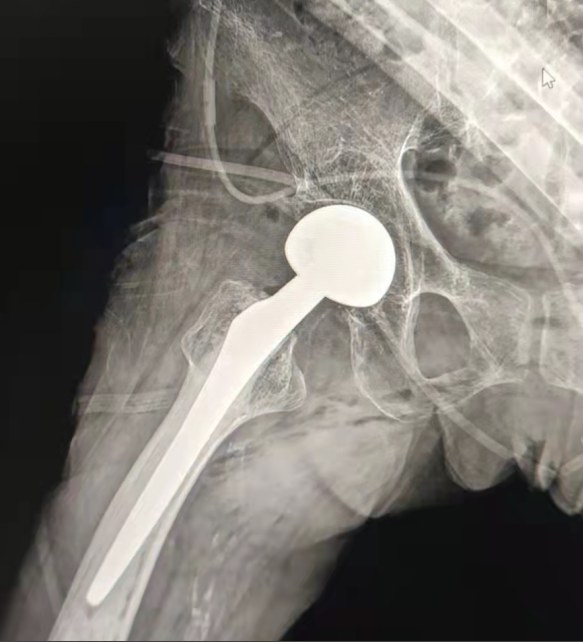

Case Sharing | Paciente de 70 anos, recebeu a substituição total do quadril com sistema de quadril cimentado Lepu

Sistema quadril cimentado:

Materiais liga Co-Cr-Mo

Alta resistência ao desgaste

Grande resistência mecânica

Projeto do fio do ombro

Instale, segure e ajuste facilmente o ângulo

Tratamento superfície polido

Para alcançar excelente crescimento ósseoGarantir a estabilidade da fixação precoce

12/14 Projeto padrão do atarraxamento

Proximal Mix Anatomy

Coleção Design Europa e EUA Stem Features

Distal ambos os lados Adge corte tratamento

Reduzir a pressão na cavidade medular